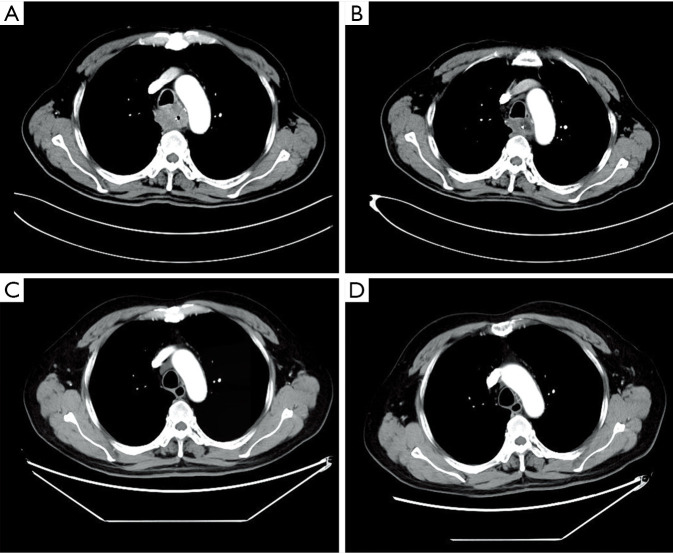

Considering the high risk of surgery, the patient received nasogastric tube placement and chemotherapy involving the administration of docetaxel (120 mg, day 1), nedaplatin (60 mg, days 2–3). After 3 cycles of chemotherapy, the lesion did not shrink obviously on chest enhanced CT (Figure 2A). In view of the good objective response rate (ORR) of camrelizumab in the phase 1 trial, the patient agreed to receive immunotherapy with camrelizumab. After 1 cycle of monotherapy with camrelizumab, the lesion shrank slightly based on chest CT (Figure 2B). Therefore, another 2 cycles of monotherapy with camrelizumab were administrated. To further improve the efficacy, the patient received 8 cycles of combination therapy with camrelizumab (200 mg day 1) and docetaxel (120 mg day 2) from November 2017. In January 2018, the nasogastric tube was removed. The patient can take some semi-liquid food. Then, 6 cycles of monotherapy with docetaxel as maintenance therapy were administrated. On August 17, 2018, there was no abnormal lesion found in the esophagus according to chest CT (Figure 2C). Dysphagia score improved to 1 score. On April 22, 2019, complete response was still observed on chest CT (Figure 2D). On November 14, 2019, the gastroscope examination indicated smooth mucosa of the esophagus (Figure 1B). Temporary grade II adverse event of reactive capillary hemangioma was observed during the treatment. By November 14, 2019, the PFS exceeded 28 months, and the patient is still being followed up. The treatment processes of the patient were shown in Figure 3.

Figure 2.

Chest computed tomography scan. The lesion in the upper esophagus on August 8, 2017 (A). The lesion shrank slightly on October 7, 2017 (B). There was no abnormal lesion on August 17, 2018 (C). complete response was still observed on April 22, 2019 (D).